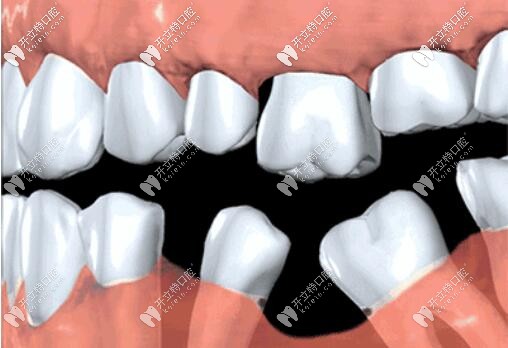

很多人覺(jué)得缺一兩顆牙沒(méi)事,殊不知,長(zhǎng)期咬合不平衡,導(dǎo)致缺牙部位鄰牙傾倒,對(duì)頜牙伸長(zhǎng),整口牙不整齊,都會(huì)影響口腔健康牙齒,加快其他牙脫落。

QQ截圖20200722101046.jpg

而且牙齒缺失牙槽骨很快萎縮,再想種牙,有可能骨量不夠,需要植骨,增加額外費(fèi)用,所以缺牙一定要及時(shí)鑲牙,不單是為了健康,也為了幫你省錢(qián)。